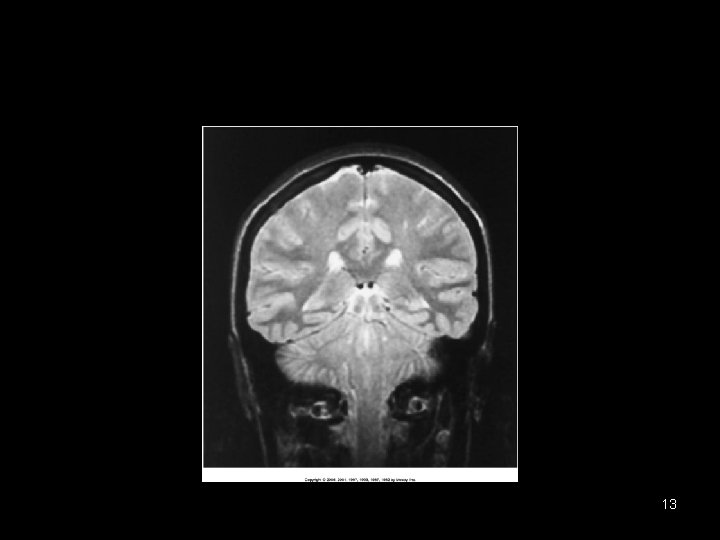

Coronal 12

Coronal 14